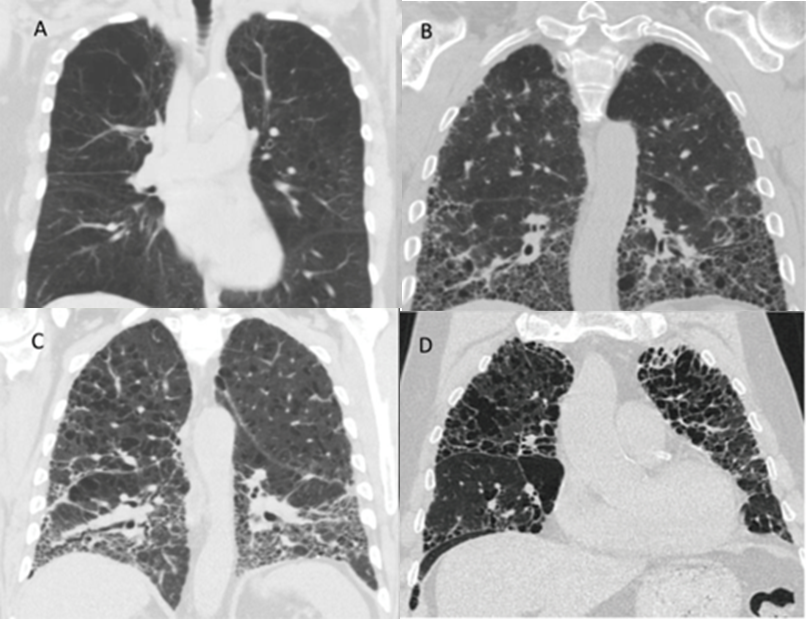

Various CT imaging patterns have been observed in patients with combined emphysema and fibrosis (Figure 1). Patients may demonstrate predominantly emphysema in the upper lobes and predominantly pulmonary fibrosis in the lower lobes (Figure 1C), emphysema in the upper lobes with diffuse ground-glass opacities and fibrotic change both in the upper and lower lobes, or enlarged emphysematous spaces surrounded by thickened fibrotic walls often in a predominantly upper lobe distribution (Figure 1D). In this latter pattern, the findings of emphysema and fibrosis exist in a similar geographic distribution within the lung, and this pattern has often been referred to as airspace enlargement with fibrosis [58,59]. Each of these different radiographic patterns can be described under the broad heading of CPFE, which highlights the lack of a universal precise characterization of patients with CPFE. One could speculate on whether there is a correlation between a particular imaging pattern and a particular timeline of disease development as described in the preceding paragraph, but an accurate association in this regard is unknown at present.

Figure 1.

Representative chest computed tomography (CT) images from selected patients from the authors’ institution with emphysema alone (A), pulmonary fibrosis alone (B), upper lobe emphysema with lower lobe pulmonary fibrosis (C), and upper lobe emphysema with thickened fibrotic walls, also referred to as air space enlargement with fibrosis (D).